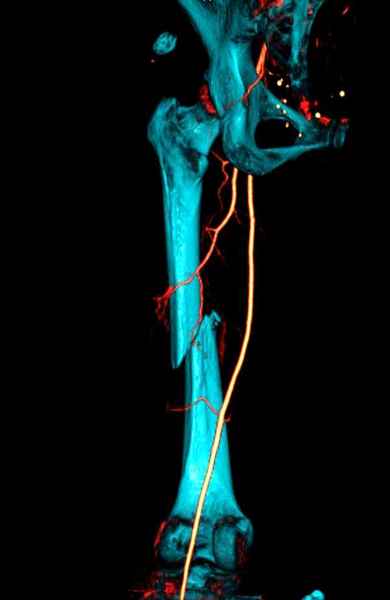

Для предупреждения кровотечения во время рассверливания, за день до операции провели эмболизацию сосудов питающий метастаз. http://radiology.rsnajnls.org/cgi/reprint/150/3/673.pdf (7-11, 12-15-16)

С минимальным рассверливанием и ретроградным методом провели остеосинтез бедра 12 мм гвоздем. (17-20)

Кровопотеря во время операции меньше 100 мл.